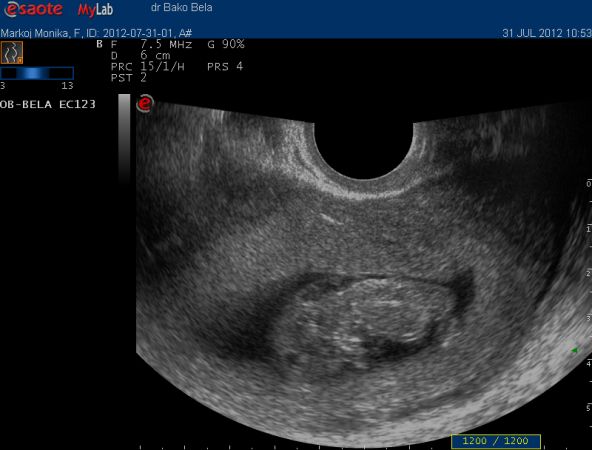

Tehat delelott korhaz, ja es ultrahang volt, izgett mozgott a beby

Reggel megyek egy talalkara mert tartoznak es ha minden igaz az ismerosom meg adja holnap, aztan 10.30ra megyek nyakiredo meresre ultrahangra.

Holnap ha tudom leirom a nyakiredo eredmenyt, gondoljatok ram!!